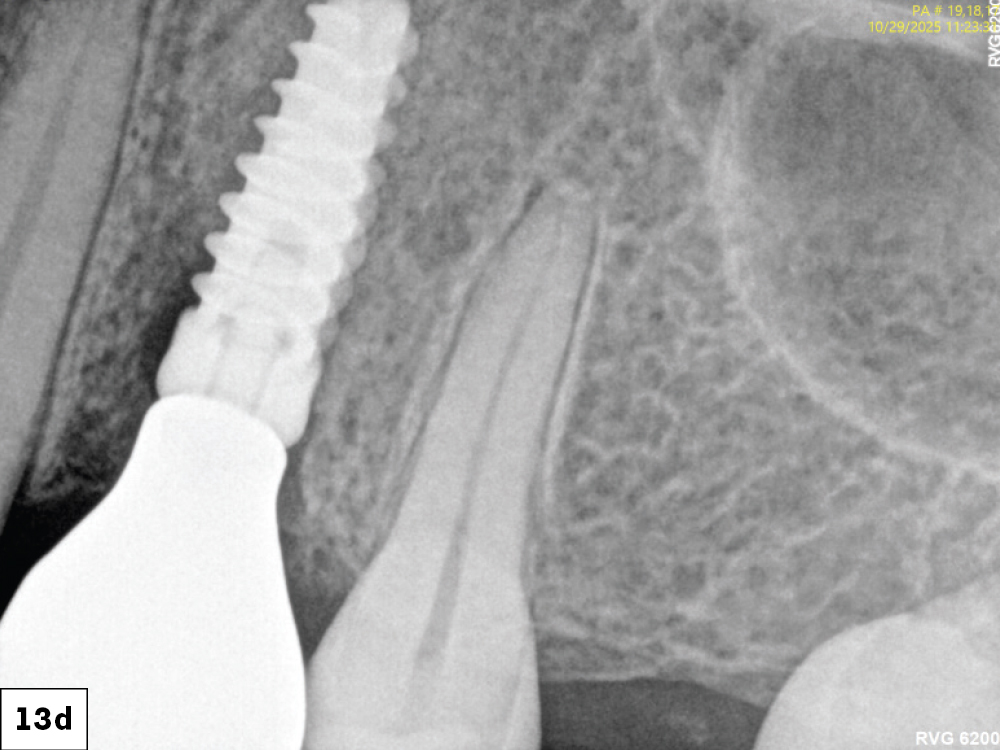

At the one-week follow up, both implants demonstrated excellent integration with healthy peri-implant tissues and no inflammation-a

At eight weeks, mature keratinized mucosa framed the zirconia crowns with stable crestal bone levels and ideal emergence profiles were confirmed radiographically-c

Figures 13a–13d: At the one-week follow up, both implants demonstrated excellent integration with healthy peri-implant tissues and no inflammation. At eight weeks, mature keratinized mucosa framed the zirconia crowns with stable crestal bone levels and ideal emergence profiles were confirmed radiographically.